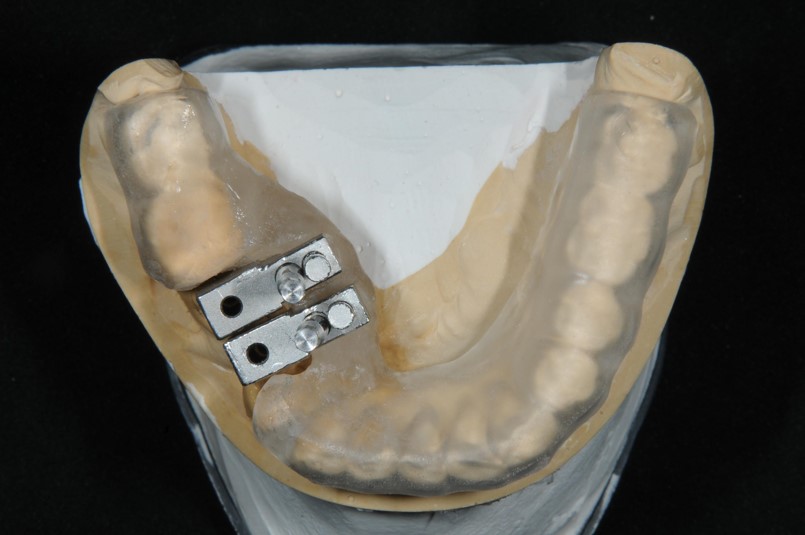

植牙用手術定位器

植牙用手術導板